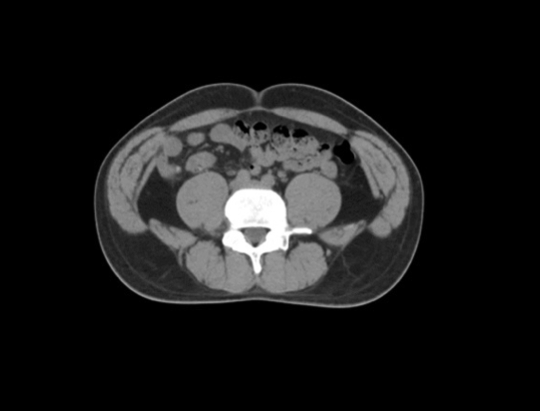

2021年3月2日早9点,这一畅想迎来了首次临床检阅:医生、物理师、技术员三方首次汇聚在控制室内,运用All-In-One一站式放疗技术为一例直肠癌患者进行首次放疗。CT模拟定位、智能勾画与审核修改、自动计划、自动复位、计划评估与审核、CT影像引导、治疗与EPID实时剂量监测质控依次在紧张有序地操作下进行,整个流程在23分钟内一气呵成,颠覆了传统至少数天才能完成的首次放疗流程。这是应用人工智能技术打造的全新肿瘤治疗模式,自此开启肿瘤诊疗智能2.0时代。